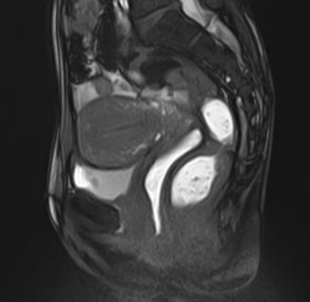

position NEUTRE

Position de repos de la patiente.

position POUSSEE 1

Effort de poussée :  les organes vessie, vagin et rectum descendent. le radiologue peut déterminer par différentes mesures l'importance du prolapsus.